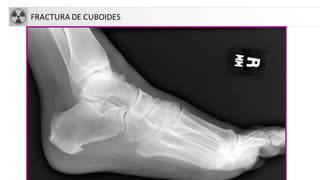

FRACTURA DE CUBOIDES

FRACTURASDEL TARSO

• Calcáneo

• Fx más frecuente del tarso y 2% del total.

• 75% intraarticulares.

• Mecanismo: caida de talones.

• Rx: disminuciónángulo de Böhler (normal 25-40º).